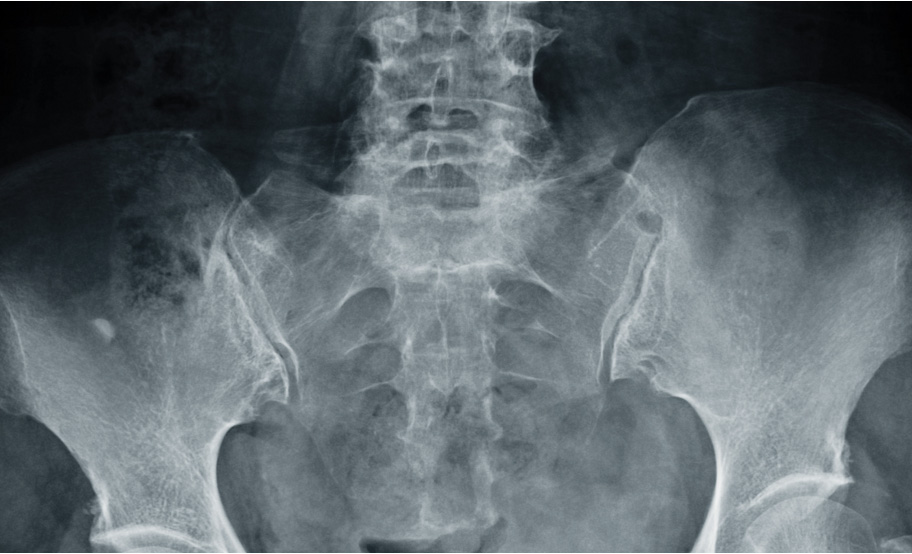

A combination of SpA features* and imaging distinguishes nr-axSpA from AS.1,3

The clinical diagnosis of axSpA is often informed by imaging findings.4 axSpA can be divided into two subgroups, nr-axSpA and AS (also called radiographic axSpA), based on evidence of radiographic sacroiliitis by mNY grading.3,†

Sacroiliitis evident on MRI and ≥1 SpA feature1,*ORHLA-B27 positivity in combination with ≥2 other SpA features1,*ANDNo evidence of definite structural damage on X-ray imaging1

≥1 SpA feature1,*ANDSacroiliitis: grade ≥2 bilaterally or grade 3/4 unilaterally1,3